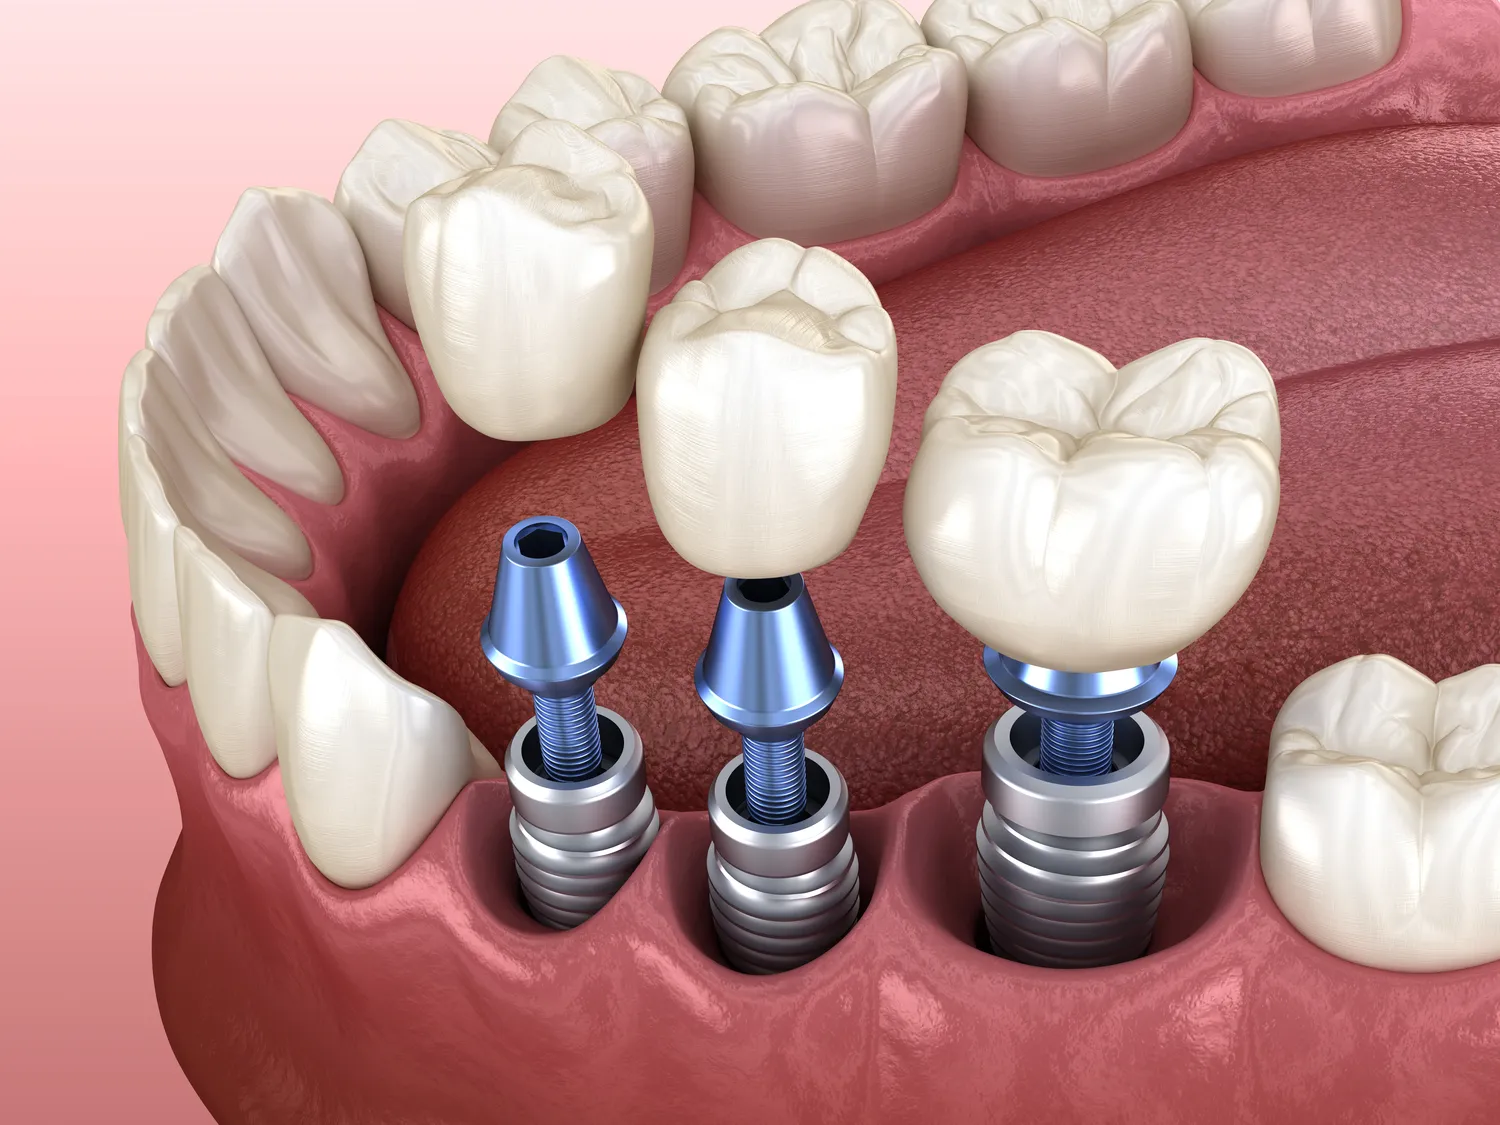

Implanty zębów to nowoczesne rozwiązanie, które pozwala na odbudowę brakujących zębów w sposób trwały i estetyczny. Niemniej jednak, nie każdy pacjent jest odpowiednim kandydatem do ich wszczepienia. Istnieje wiele przeciwwskazań, które mogą uniemożliwić przeprowadzenie tego zabiegu. Przede wszystkim, jednym z najważniejszych czynników jest stan zdrowia pacjenta. Osoby cierpiące na choroby przewlekłe, takie jak cukrzyca, choroby serca czy schorzenia autoimmunologiczne, mogą mieć zwiększone ryzyko powikłań pooperacyjnych. Dodatkowo, palenie papierosów znacząco wpływa na proces gojenia się tkanek oraz może prowadzić do niepowodzeń w integracji implantu z kością. Innym istotnym aspektem są problemy z jamą ustną, takie jak ciężkie zapalenie dziąseł czy nieleczone ubytki próchnicowe, które mogą stanowić przeszkodę w przeprowadzeniu zabiegu.

Wiek pacjenta jest jednym z kluczowych czynników branych pod uwagę podczas kwalifikacji do zabiegu wszczepienia implantów zębowych. U młodszych osób, zwłaszcza dzieci i nastolatków, istnieje ryzyko, że ich kości szczękowe jeszcze się rozwijają, co może prowadzić do problemów z prawidłowym umiejscowieniem implantu oraz jego stabilnością w przyszłości. Z tego powodu lekarze stomatolodzy często zalecają odroczenie zabiegu do momentu zakończenia wzrostu kości. Z drugiej strony, u osób starszych mogą występować różne schorzenia zdrowotne oraz zmiany w strukturze kości, które również mogą wpłynąć na decyzję o wszczepieniu implantu. Osoby starsze często borykają się z osteoporozą lub innymi chorobami układu kostnego, co może utrudniać proces integracji implantu z kością.

Oprócz wieku i stanu zdrowia pacjenta istnieje wiele innych czynników, które mogą wpłynąć na decyzję o wszczepieniu implantów zębowych. Jednym z nich jest jakość oraz ilość tkanki kostnej w miejscu planowanego wszczepienia. Jeśli kość jest zbyt cienka lub osłabiona, lekarz może zalecić przeprowadzenie dodatkowych zabiegów, takich jak augmentacja kości czy przeszczepy kostne, aby stworzyć odpowiednie warunki dla implantu. Kolejnym istotnym czynnikiem jest higiena jamy ustnej pacjenta; osoby zaniedbujące codzienną pielęgnację zębów i dziąseł mogą być narażone na większe ryzyko infekcji po operacji. Również stosowane leki mają znaczenie; niektóre leki przeciwzakrzepowe czy immunosupresyjne mogą wpływać na proces gojenia się tkanek oraz zwiększać ryzyko powikłań.

Po wszczepieniu implantów zębowych, jak w przypadku każdego zabiegu chirurgicznego, mogą wystąpić różne powikłania. Najczęściej spotykanym problemem jest infekcja w miejscu wszczepienia implantu. Może to być spowodowane nieodpowiednią higieną jamy ustnej lub obecnością bakterii w tkankach. Infekcje mogą prowadzić do stanu zapalnego, co z kolei może wpłynąć na proces gojenia i integracji implantu z kością. Innym możliwym powikłaniem jest brak osseointegracji, czyli nieprawidłowe połączenie implantu z kością. Może to być wynikiem niewystarczającej ilości tkanki kostnej lub problemów zdrowotnych pacjenta, takich jak cukrzyca czy palenie papierosów. W skrajnych przypadkach może dojść do odrzucenia implantu przez organizm, co wymaga jego usunięcia. Dodatkowo, pacjenci mogą doświadczać bólu lub dyskomfortu w okolicy implantu, co może być związane z nadwrażliwością tkanek lub nieprawidłowym umiejscowieniem implantu.

Przed przystąpieniem do zabiegu wszczepienia implantów zębowych konieczne jest przeprowadzenie szeregu badań diagnostycznych, które pozwolą ocenić stan zdrowia pacjenta oraz przygotowanie do operacji. Pierwszym krokiem jest dokładna analiza historii medycznej pacjenta oraz przeprowadzenie badania klinicznego jamy ustnej. Lekarz stomatolog powinien zwrócić uwagę na obecność chorób przewlekłych oraz przyjmowanych leków, które mogą wpływać na proces gojenia się tkanek. Następnie wykonuje się zdjęcia rentgenowskie lub tomografię komputerową, aby ocenić jakość i ilość tkanki kostnej w miejscu planowanego wszczepienia implantu. Badania te pozwalają również na identyfikację ewentualnych anomalii anatomicznych, takich jak bliskość nerwów czy zatok szczękowych. W niektórych przypadkach lekarz może zalecić dodatkowe badania laboratoryjne, takie jak morfologia krwi czy badania poziomu glukozy u pacjentów z cukrzycą.

Proces gojenia po wszczepieniu implantów zębowych jest kluczowym etapem, który decyduje o sukcesie całej procedury. Po zabiegu pacjent może odczuwać ból oraz dyskomfort w okolicy implantu; lekarz zazwyczaj przepisuje leki przeciwbólowe oraz zaleca stosowanie zimnych okładów w celu złagodzenia obrzęku. Gojenie tkanek miękkich trwa zazwyczaj od kilku dni do dwóch tygodni, jednak pełna integracja implantu z kością – proces znany jako osseointegracja – może trwać od kilku tygodni do kilku miesięcy w zależności od indywidualnych predyspozycji pacjenta oraz jakości tkanki kostnej. W tym czasie niezwykle istotne jest przestrzeganie zaleceń lekarza dotyczących higieny jamy ustnej oraz unikanie twardych pokarmów, które mogłyby wpłynąć na stabilność implantu. Regularne wizyty kontrolne pozwalają lekarzowi monitorować postęp gojenia oraz wykrywać ewentualne komplikacje na wczesnym etapie.